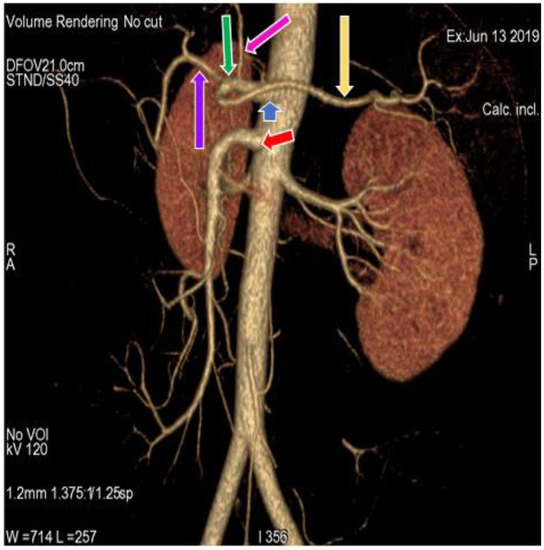

3.1. Variation in Origin and Branching Pattern of Celiac Trunk

3.2. Variation in Origin and Branching Pattern of Hepatic Artery